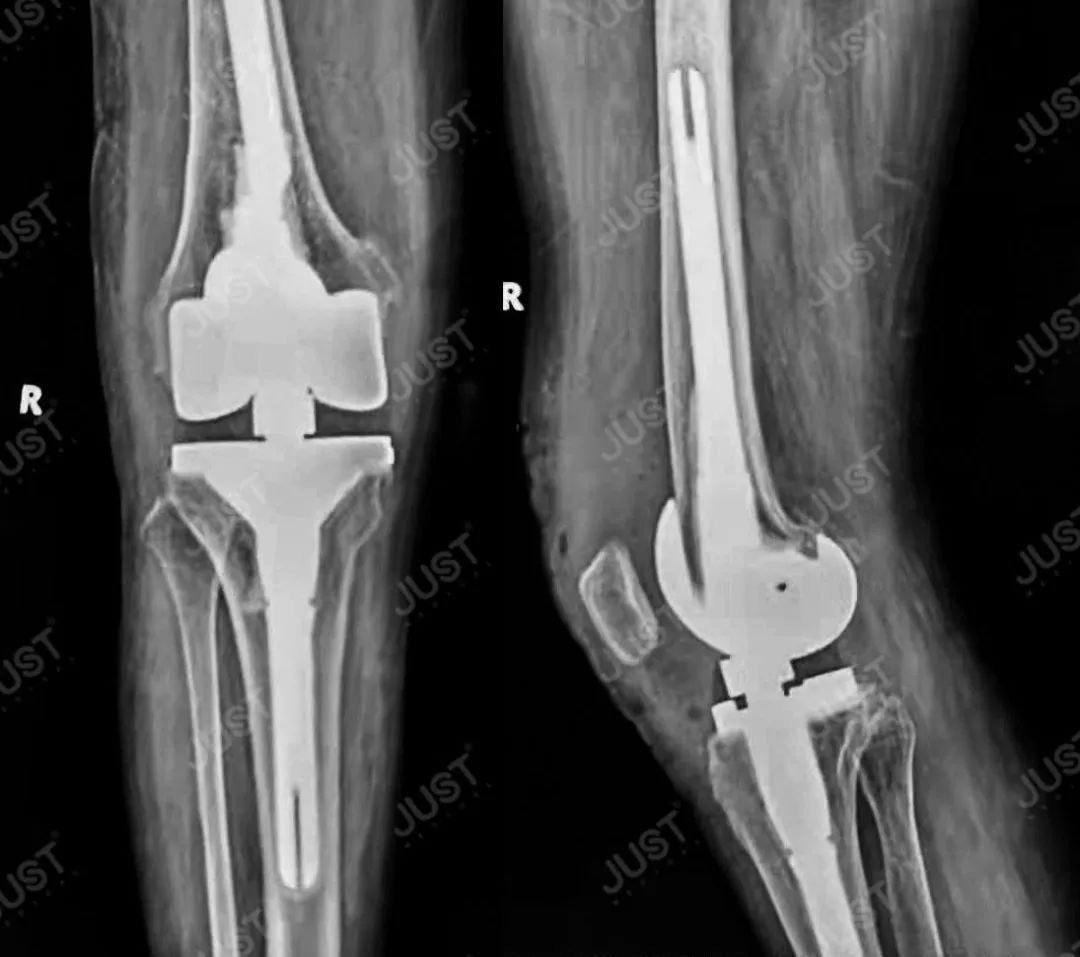

假体植入实例HRSK旋转铰链膝关节假体系统

术后资料

嘉思特医疗HRSK翻修全膝关节系统与RSK翻修全膝关节系统工具通用,避免术中复杂的工具操作,14-22mm多型号平台垫片以及百余种垫块纠正关节线,铰链轴的结构实现膝关节的高屈曲,允许膝关节内旋、外旋20°,活动自如!